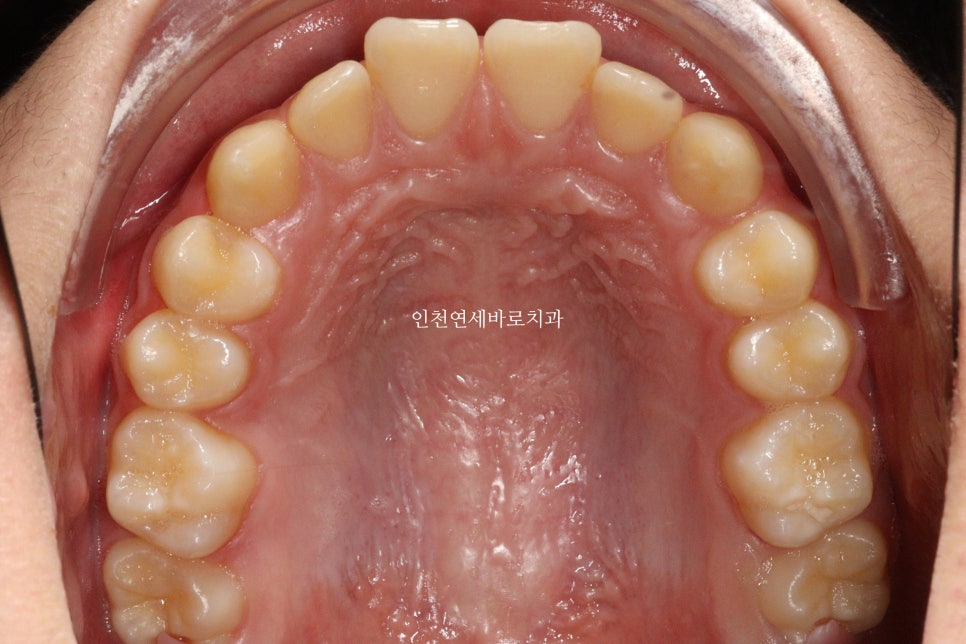

치료 전과 후 입니다.

앞니가 후방이동 한것이 확인됩니다.

우리는 부분교정을 한것이 아니라 간단한 전체교정을 한것입니다.

전과 후의 얼굴 변화입니다.

치아가 들어가보입니다.

앞니만 철사를 붙여서는 얻기 어려운 결과라고 생각합니다.